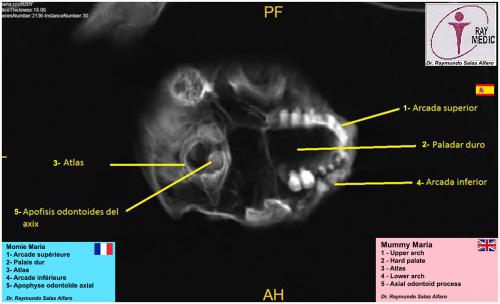

Planches (Dr José Rios de la Cruz) - Scanners (Dr Raymundo Salas Alfaro)

Scanners et radios de la grande "MARIA" de 168 cm

(cliquer sur les planches pour les agrandir)

Mâchoire